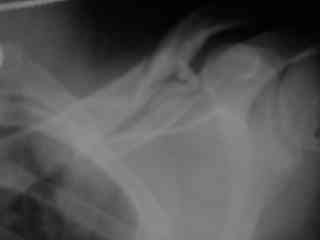

C> Postupil ko mne bolnoi s perelomom obeih kluchits, neznachitelny

C> pneumotorakx sleva.

Bolnogo operirovali plastinami, snimky zdes'.

CIMG1145.JPG